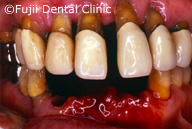

| 術後パノラマ写真および口腔内写真 |

ヘビースモーカーであったために、禁煙してもらい、歯のクリーニングやブラッシング指導後、およそ2年間かけて左上犬歯と左下第一小臼歯以外すべての歯を抜歯し、インプラントの埋入手術を行いました。左右上顎臼歯部はサイナスリフトなどを併用し、インプラントによる咬合の再構築を試みました。